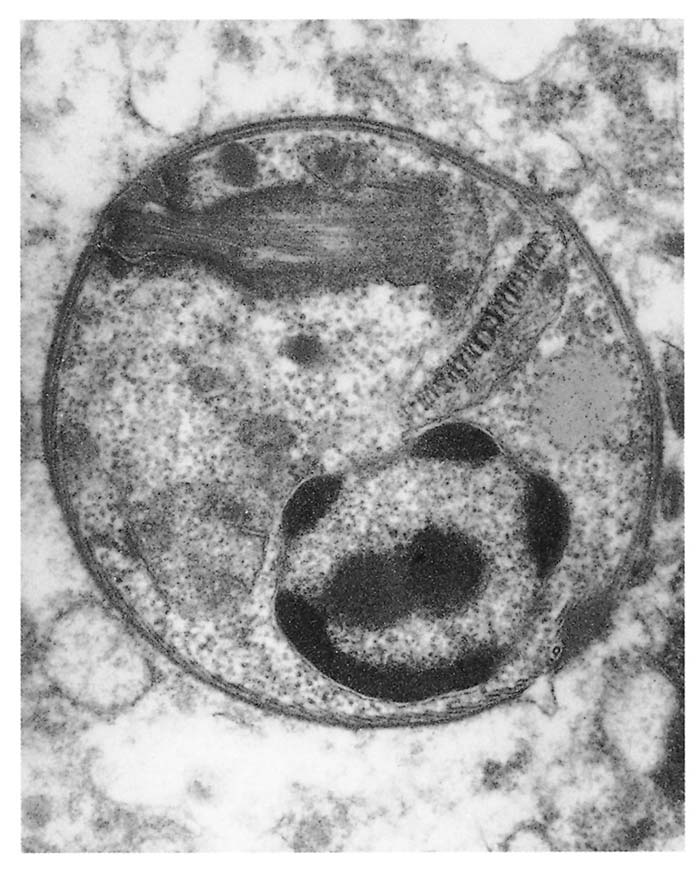

The parasite occurs in two forms: a promastigote stage which is found in the sandfly; and an amastigote stage which occurs in the mammalian host. During feeding, the infected sandfly injects promastigotes into the dermis of the mammalian host and these are engulfed by phagocytic cells before transforming into amastigotes which multiply by binary fission. Heavily parasitized host cells eventually rupture, and the liberated amastigotes invade other macrophages in which they may be spread locally or systemically.17 In tissues, amastigotes of all Leishmania spp. are morphologically similar (Figure 22.2 and Figure 22.3): they are round to oval bodies, 1,5–3 × 2,5–6,5 μm in diameter, containing a single nucleus and a rod-shaped kinetoplast.17